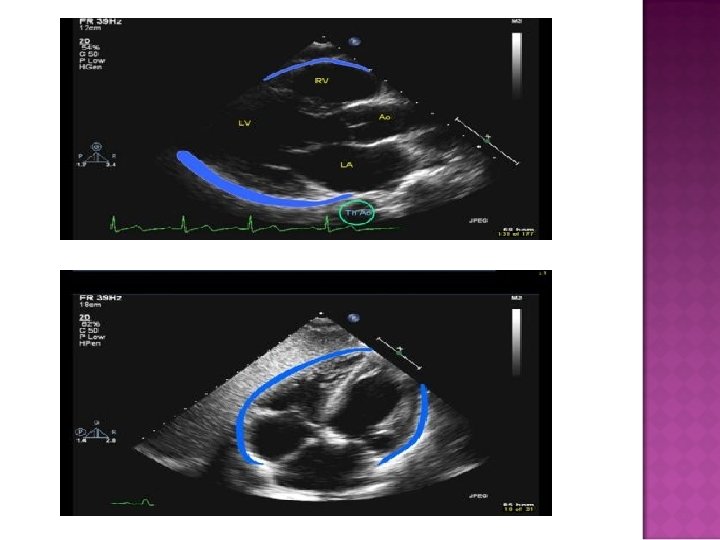

� M-Mode

� M-mode Cannot determine volume of accumulated fluid accurately

� Normal amt of pericardial fluid = 20 -50 m. L � Tamponade occurs when lg or rapidly formed effusions inc’d pressure in the pericardial space throughout the cardiac cycle � During inspiration, RV volume inc’s & in tamponade, the RV is unable to expand into the maximally stretched pericardium Lward bulging of the interventricular septum dec’d LVEDV dec’d cardiac output & dec’d SBP during inspiration

�Pressure in pericardium exceeds s �Compressive effect in intrachamber �Diagnostic techniques � 2 D looking for RA/RV collapse during diastole �M-mode for RA/RV collapse during diastole �Doppler of Mitral and Tricuspid inflow Mitral inflow to decrease by 25% with inspiration Tricuspid inflow increased by 40% with inspiration �IVC diameter fails to increase with inspiration